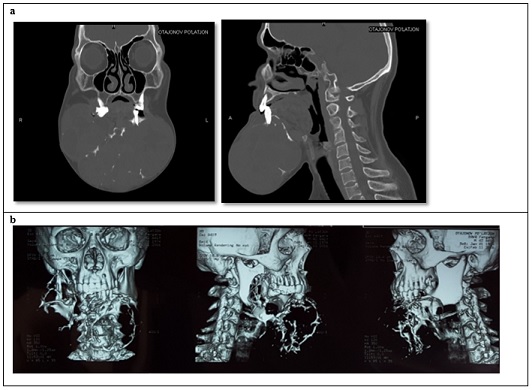

A CT scan from February 11, 2016, showed a large, 14.4x10 cm mass in the projection of the mandible with a heterogeneous structure and a cystic component of +9 to +24 to +41 Hounsfield Units with irregular contours (Figure 2). Preoperative histology (No 1123 b/16) confirmed Ameloblastoma.Based on the research data obtained, the following preoperative diagnosis was established: Ameloblastoma of the mandible (Solid type). Status post three surgeries (2003, 2006, 2008 in Fergana). Recurrence, locally advanced form.

Figure 2a: CT scan in two projections. Large formation in the mandible region. 2b. Three-dimensional reconstruction of the patient's computed tomography scan.Figure 2a: CT scan in two projections. Large formation in the mandible region. 2b. Three-dimensional reconstruction of the patient's computed tomography scan.